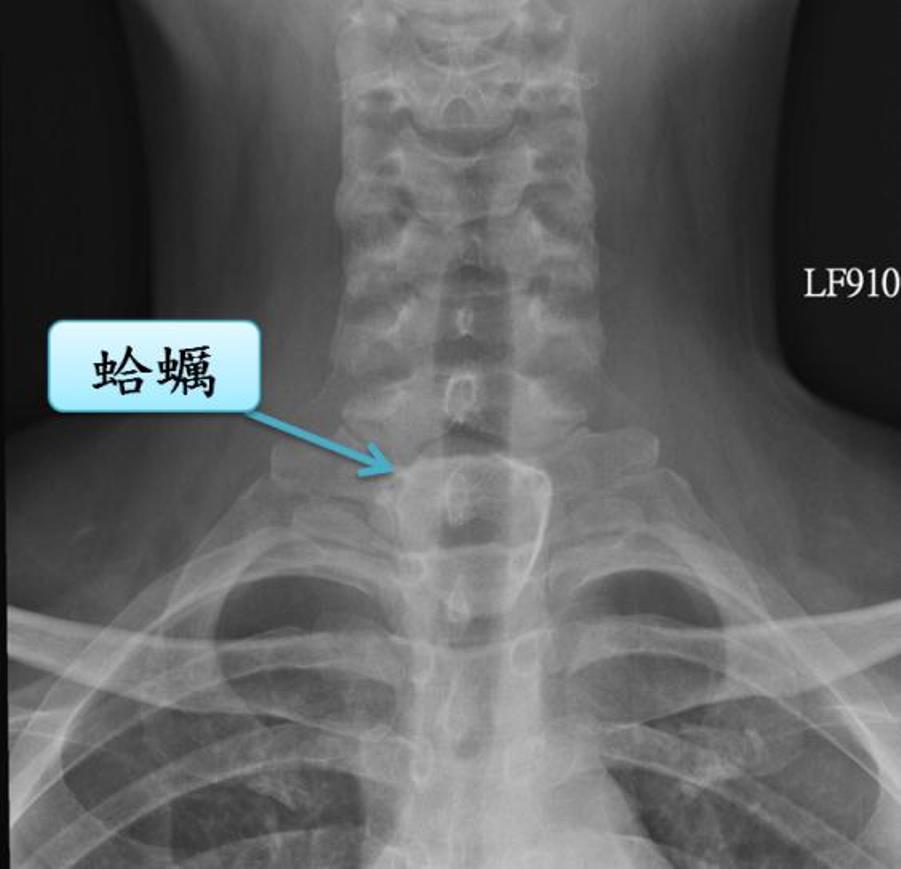

許秉毅提到,曾遇到1位年輕的男性勞工朋友,早餐吃「海鮮粥」,因趕著上班,將剩下的粥一大口吞下去,突然間覺得頸部不舒服,且吞不下東西,趕緊去診所檢查,發現食道被4公分寬的蛤蜊給哽住。

經過10幾天,經胃鏡檢查,發現蛤蠣殼已造成食道深度潰瘍及出血,會診胸腔科醫師以手術方式取出,並修補食道裂傷。

▲蛤蠣殼已造成食道深度潰瘍及出血。(圖/安南醫院提供)